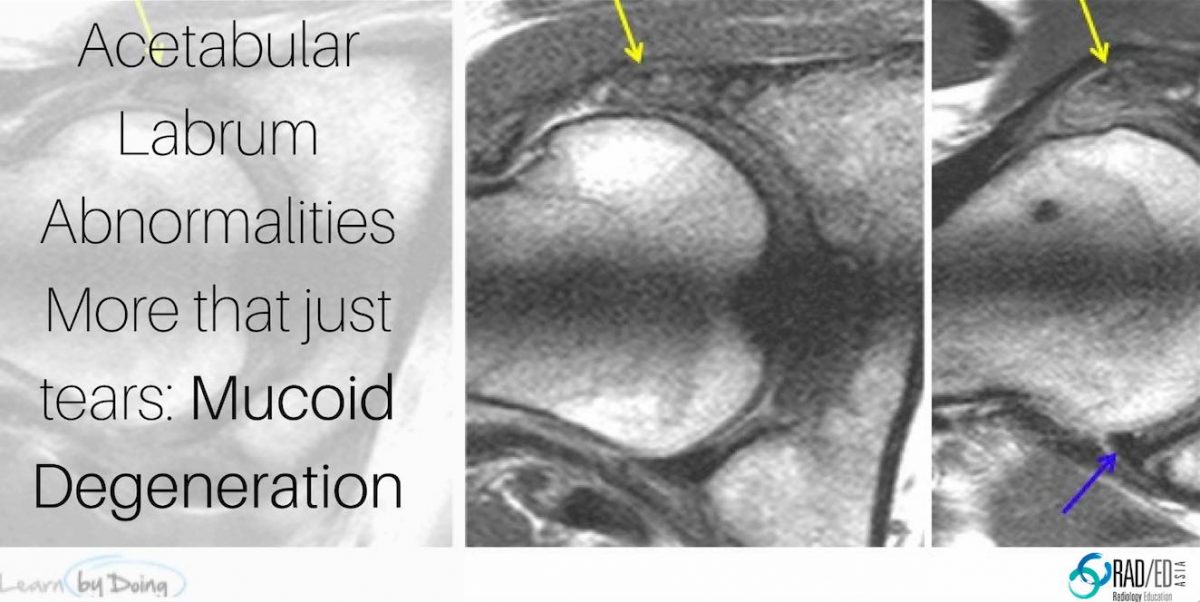

Hip Acetabular Labrum MRI More than just tears Mucoid Degeneration What Does Fraying Of The Labrum Mean A hip labral tear occurs when the labrum of the hip tears or detaches from the rim of the acetabulum. For example, wear and tear from frequent kicking or dancing may cause a few centimeters of the labrum to. The most common symptoms of a labral tear in your hip include: Like the gaskets that seal the joints between the. What Does Fraying Of The Labrum Mean.